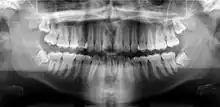

Orthopantomograms (OPTs) are used by health care professionals to provide information on:

- Impacted wisdom teeth diagnosis and treatment planning - the most common use is to determine the status of wisdom teeth and trauma to the jaws.

- Periodontal bone loss and periapical involvement.

- Finding the source of dental pain, and when carrying out tooth-by-tooth diagnosis.

- Assessment for the placement of dental implants

- Orthodontic assessment. pre and post operative

- Diagnosis of developmental anomalies such as cherubism, cleido cranial dysplasia

- Carcinoma in relation to the jaws

- Temporomandibular joint dysfunctions and ankylosis.

- Diagnosis of osteosarcoma, ameloblastoma, renal osteodystrophy affecting jaws and hypophosphatemia.

- Diagnosis, and pre- and post-surgical assessment of oral and maxillofacial trauma, e.g. dentoalveolar fractures and mandibular fractures.

- Salivary stones (Sialolithiasis).

- Other diagnostic and treatment applications.[2]